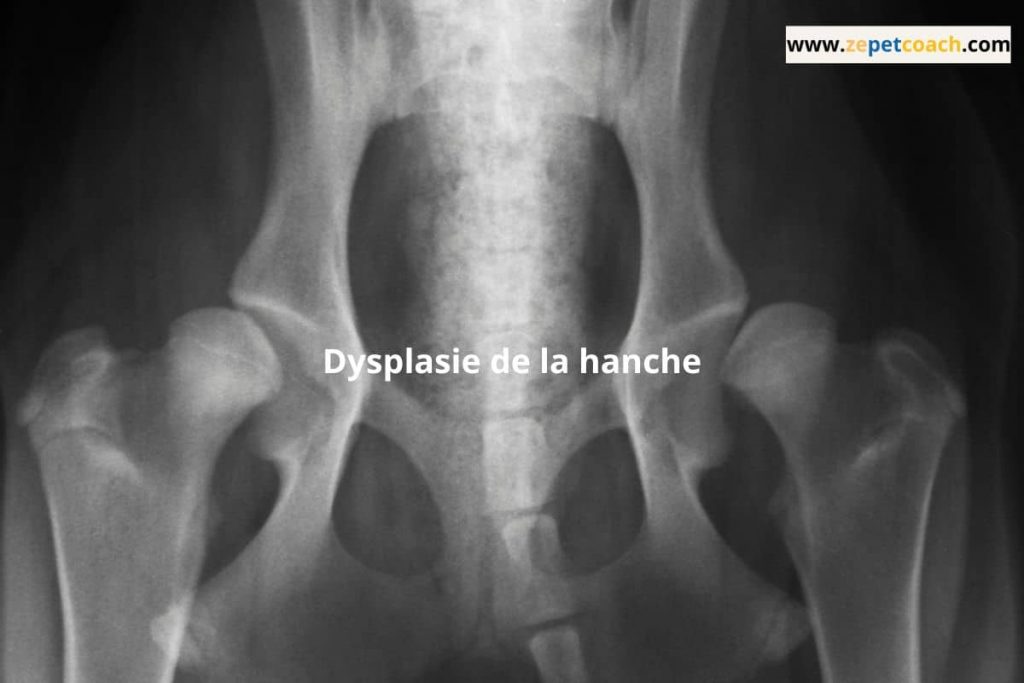

La dysplasie se caractérise par une malformation de l’articulation de la hanche, entraînant des problèmes de mobilité et des douleurs chroniques. Diagnostiquer précocement cette maladie est crucial pour limiter ses effets débilitants. Les vétérinaires s’appuient sur des radiographies pour évaluer la gravité de la dysplasie et déterminer le traitement approprié, qui peut aller de la gestion de la douleur à une intervention chirurgicale. Comprendre cette pathologie vous permettra de mieux accompagner votre chien dans sa prise en charge.

Le diagnostic de la dysplasie de la hanche commence souvent par un examen physique, où le vétérinaire inspecte les hanches et observe la démarche de l’animal. Des radiographies sont généralement nécessaires pour confirmer le diagnostic, permettant ainsi de visualiser l’articulation et d’évaluer la gravité de la dysplasie. Dans certains cas, une échographie ou une IRM peut être envisagée pour obtenir des images plus détaillées. L’analyse génétique peut également être utile pour déterminer la prédisposition. Un diagnostic précoce est crucial pour instaurer rapidement un plan de traitement efficace et améliorer la qualité de vie de l’animal.